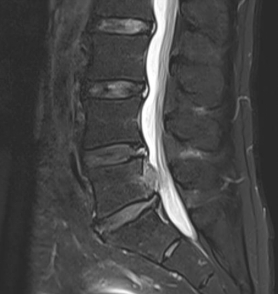

如果说UBE技术是脊柱治疗的“精准镜手”,那么3D打印技术就是定制化治疗的“私人裁缝”。针对每一位脊柱疾病患者的个体差异,医生通过高精度CT扫描,获取患者脊柱的三维立体数据,利用3D打印技术1:1还原脊柱的解剖结构——从椎体形态、椎间盘位置,到神经走行、病变范围,都能精准复刻,形成专属的脊柱模型。基于此模型,医生术前可以进行精准规划:模拟手术路径、预判操作风险、选择适配的内固定器械,甚至打印定制化的椎间融合器、内固定支架,确保手术操作“有的放矢”,贴合患者的个体解剖特征,避免传统手术中“凭经验操作”的不确定性,让脊柱治疗从“标准化”走向“个性化”,极大提升了手术的精准度与安全性。